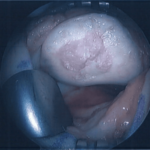

Cartilage defect of the trochlea

(underneath the knee cap)

Cartilage defect debrided for clean edges

New cells implanted and sealed with fibrin glue